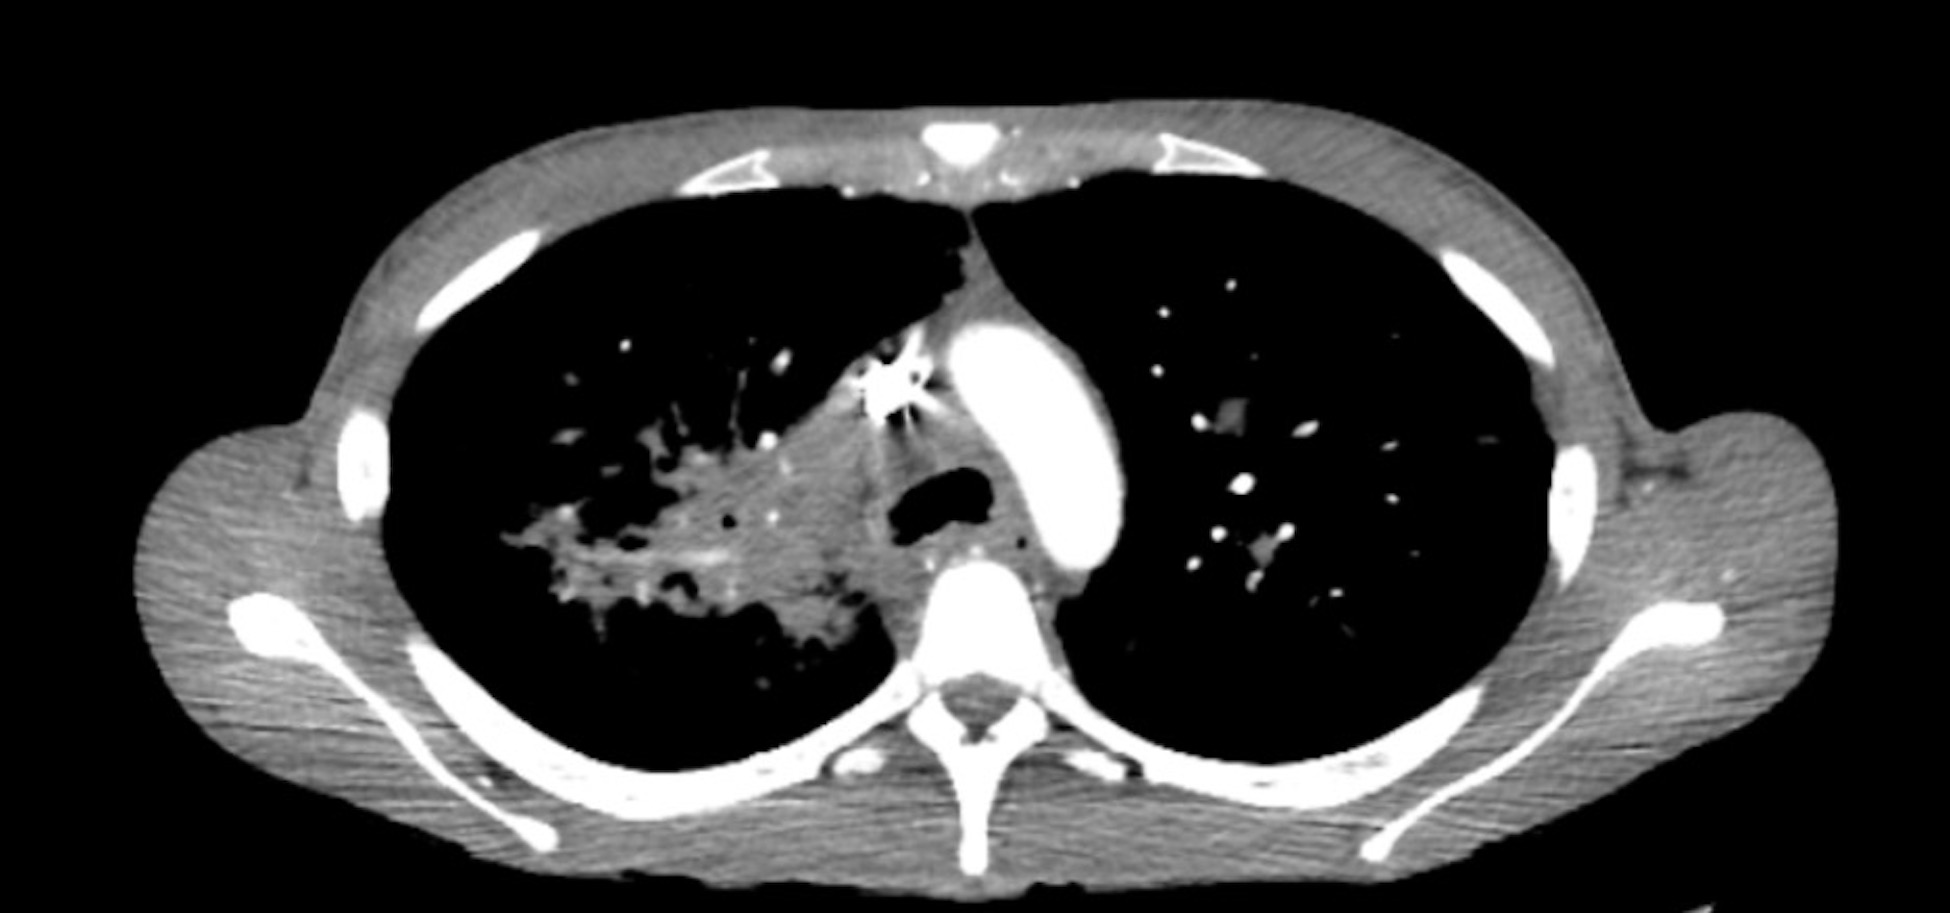

Sarcoidosis is a multisystem inflammatory disease characterized by non-caseating granulomas, primarily affecting the lungs but also involving other organs such as the skin, eyes, and heart.1 Due to its variable presentation, diagnosing sarcoidosis in the emergency department (ED) can be challenging. We report a case of a 28-year-old African American female presenting with acute dyspnea on exertion, significant weight loss, and multiple cutaneous nodules. Her diagnostic workup revealed hypercalcemia, diffuse pulmonary nodules, and extensive lymphadenopathy on imaging. Biopsy of her eyelid lesions confirmed non-caseating granulomas, leading to a diagnosis of sarcoidosis. She was initiated on high-dose steroids and evaluated for further immunologic therapy. Sarcoidosis presents a diagnostic challenge due to its nonspecific symptoms, often mimicking more common conditions.2 Early recognition in the ED is critical to prevent disease progression. This case underscores the importance of considering sarcoidosis in patients with unexplained systemic symptoms and highlights the need for a multidisciplinary approach to management.